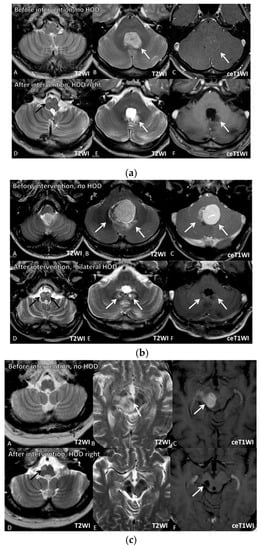

3.6. Image Series before and after HOD Development